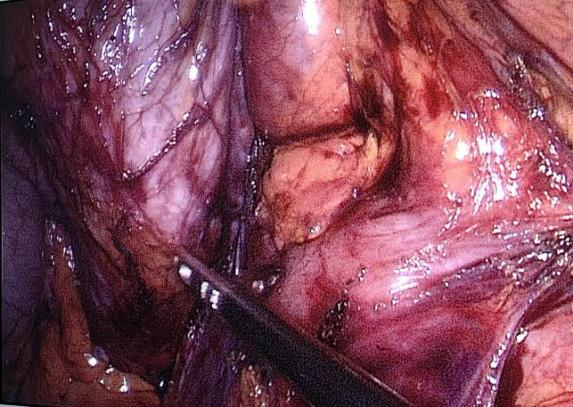

我院普外三科邵学谦主任及其团队手术画面

入院后完善相关检查,经介入团队留置肠梗阻导管(经鼻型、经肛型),肠梗阻导管由硅橡胶制成,富于柔韧性,有效吸引肠道内容物,充分减轻肠道压力、肠道准备,为患者能够行全腹腔镜全结肠切除提供了重要的先决条件。我院普外三科邵学谦主任及其团队在手术室团队的协助下完成了全腹腔镜下全结肠切除术。术后患者病情恢复良好,便秘症状得到了完全缓解,生活质量得到了显著提高。

全腹腔镜全结肠切除术涉及区域广、跨度大,需要从根部结扎的血管数量多,相当于完成了几个大型的肠道手术包括右半结肠切除、横结肠切除、左半结肠切除术,术中容易出血,处理血管的技术要求高,需要手术医生极好的耐心、细心及极强的手术技能。全腹腔镜结直肠手术的肠段切除、系膜裁剪、淋巴结清扫和消化道重建均在腹腔镜下完成。随着腹腔镜技术和吻合器械的进步,腔内吻合可减少肠管及系膜游离的范围,降低损伤肠管血供和功能的风险,减少对系膜的牵拉以及对切口长度的依赖等特点。因此,全腹腔镜手术的应用正逐渐增多。全腹腔镜全结肠手术过程中还需阶段性改变术者、助手及扶镜手站位和患者的体位,改变主操作孔和监视器的位置,对术者的技术和团队的整体配合度要求较高,是一项难度大、极复杂的腹腔镜胃肠手术。目前,我院普外三科常规开展腹腔镜肝胆胰手术、腹腔镜胃肠手术、腹腔镜疝手术、腹腔镜处理各类急腹症(消化道穿孔、肠梗阻等)的手术,为齐市患者提供微创手术平台。